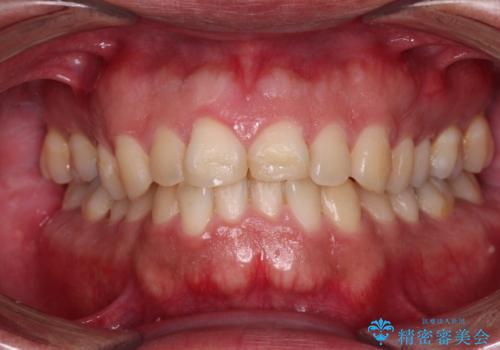

自転車で転んで前歯を損傷 前歯のオールセラミッククラウン

事故後に受診した病院の歯科にて前歯2本の欠損した部分を修復されておりましたが、見た目が気になるとのことで、オールセラミッククラウンにて補綴治療を行うこととしました。

- 治療費の目安: 66万円(税込)費用は治療当時の料金となります